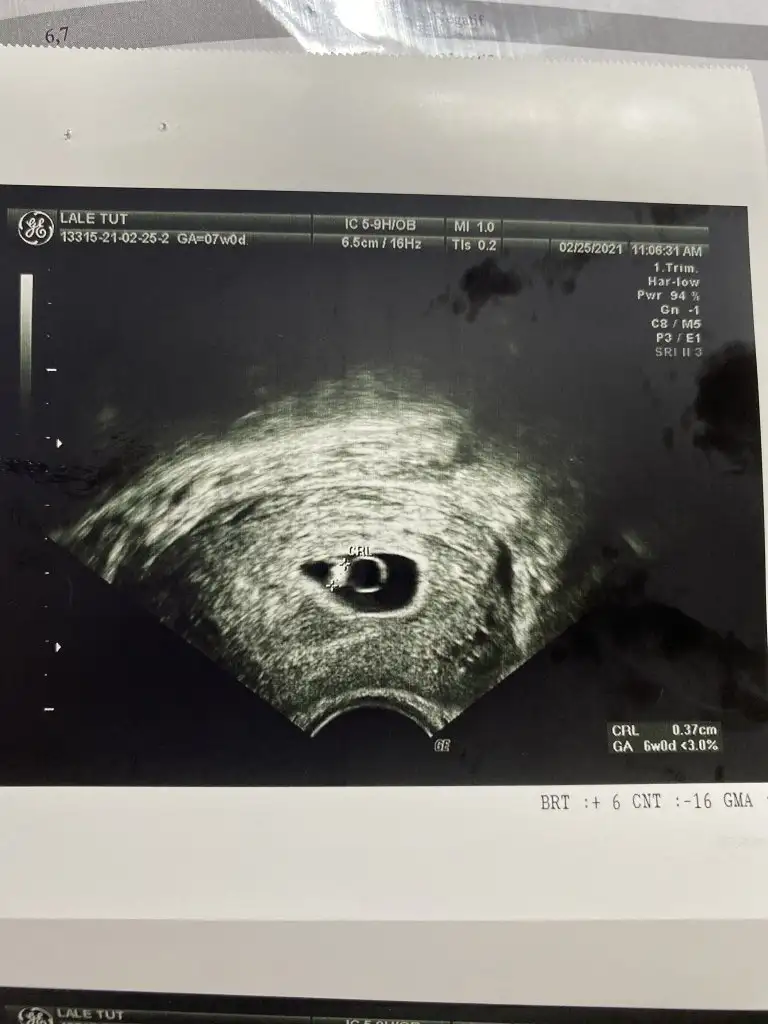

Kizlarrrr bugun 7 haftadayim ve tektasımı gördüm kalbini duydummm cok güzel bir duygu insallah sizde duyarsınız. Ultrasonda goremedi karindan vajinal baktı hatta goremedi diye saglikli degil kurtaj olman gerekir flan dedi sinirlerimi bozdu ama duydum şükür sesiniben 7 ye girdim ama ultrasonun alt kisminda 6 week yaziyor bir hafta geriden mi geliyor yani. Ben kalbinin sesini duyunca doktora hicbisey sormadim o sesi duyunca bende hersey bitti. Bide vajinal bana zor geldi onun stresi panigi bitirdi beni

Benimde tam 2 kat olarak artmadı. 6 haftadan sonra 4 günde iki kat bile yükselmedi şuan 9. Haftadayım ve kalp atışını da duyduk şükür. Doktoruma söylediğimde her zaman kitaptaki gibi olmuyor dediKizlar 6+2 hamileyim kese görünmemişti 18 subatta 3800 cıktı beta bugun 25 subat 10.000 kese minik ama cok net birşey söylemiyorlar kanamam oldu cok az hastanedeyim 10.000 cok mu az artis lütfen fikirlerinize ihtiyacım var dr ameliyattaymış çıkmasını bekliyorum

Ben de 6+2 yim karindan görünmedi vajinal bakarak 5.6mm kese gördü ama ici boş bebek görünmedi kanama alanli minik bir kese bana da haftaya gel gelişmemişse belli olur alıcaz dedi rabbim mucizesini gostersin inşallah hepimizeMerhaba benimde bugün 7+1di ama karından göremedik vajinal baktırmadım boş gebelik yada daha küçük olduğu için görünmedi doktor sizede mi öyle denildi vajinada baktırdınız